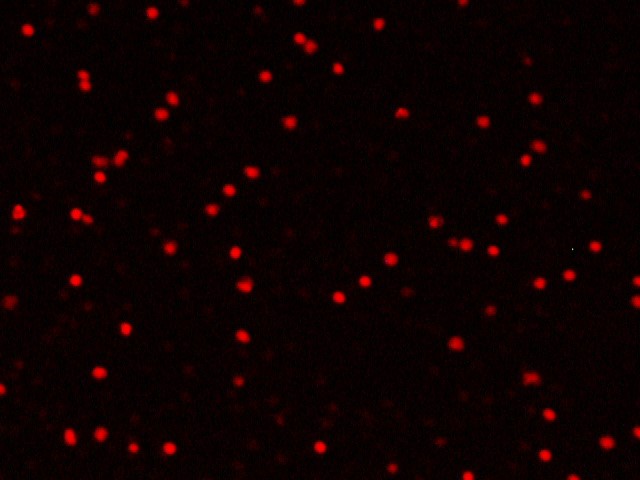

После введения цитопротекторов в лунки с лейкоцитарной взвесью пациентов с ИБС в «терапевтической концентрации» обнаружили два варианта изменения индекса жизнеспособности – в виде его повышения либо снижения, что зависело от исходных показателей анализа крови больных. О цитопротекторном эффекте препарата судили исключительно в случае повышения индекса жизнеспособности, т. е. при увеличении количества живых клеток и уменьшении количества мёртвых клеток в полях зрения (рисунок 3).

Б1. Мёртвые клетки в исходном состоянии | Б2. Мёртвые клетки после введения |

Fig. 3. Cytoprotective effect of the drug (fluorescence microscopy, 200× magnification)

А1 и А2 – увеличение количества живых клеток в поле зрения после введения цитопротекторного препарата (триметазидина или этоксидола) (окраска Сalcein АМ);

Б1 и Б2 – уменьшение количества мёртвых клеток в поле зрения после введения цитопротекторного препарата (триметазидина или этоксидола) (окраска Ethidium bromide).